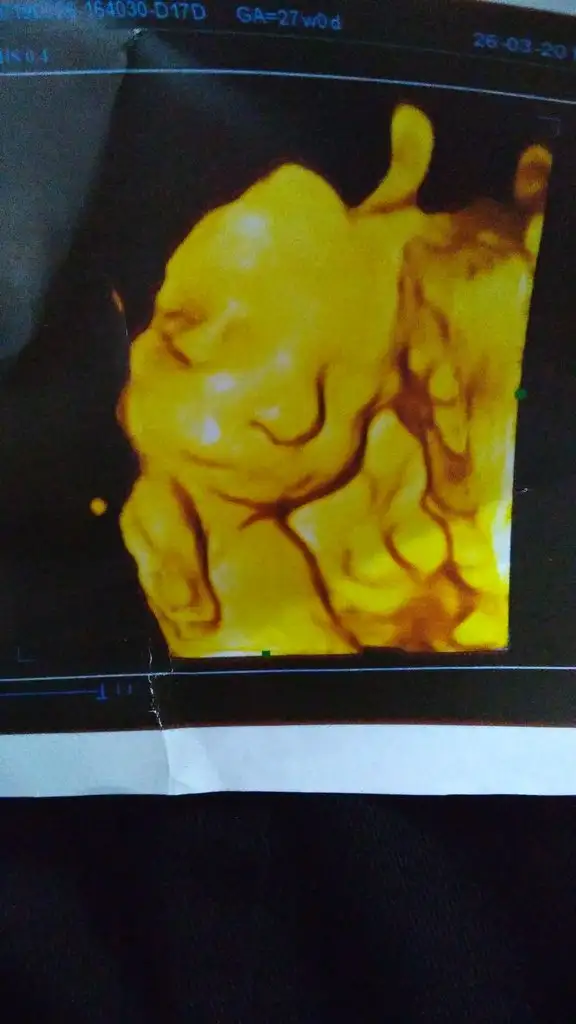

Oyy maşallah sana minikk kızTanıştırayım kızçemi teyzeleriBurnumuz azcık büyük çıkmış olabilir ama ekranda küçücüktü benim burnum gibi ucu top yüz hatları da biraz abisi biraz ben. Yani sanırım kendime benzetebildim, öyle görünüyo

oyyy masallahhh sağ salim kucagınıza alınn inşallahTanıştırayım kızçemi teyzeleriBurnumuz azcık büyük çıkmış olabilir ama ekranda küçücüktü benim burnum gibi ucu top yüz hatları da biraz abisi biraz ben. Dudağı aynı abisi ve benimki gibi üstü ince altı kalın . Yani kısacası sanırım kendime benzetebildim, öyle görünüyo

41 kere MaşallahTanıştırayım kızçemi teyzeleriBurnumuz azcık büyük çıkmış olabilir ama ekranda küçücüktü benim burnum gibi ucu top yüz hatları da biraz abisi biraz ben. Dudağı aynı abisi ve benimki gibi üstü ince altı kalın . Yani kısacası sanırım kendime benzetebildim, öyle görünüyo

Maşallah Allah sağlıkla kucağınıza almayı nasip etsinTanıştırayım kızçemi teyzeleriBurnumuz azcık büyük çıkmış olabilir ama ekranda küçücüktü benim burnum gibi ucu top yüz hatları da biraz abisi biraz ben. Dudağı aynı abisi ve benimki gibi üstü ince altı kalın . Yani kısacası sanırım kendime benzetebildim, öyle görünüyo

Tanıştırayım kızçemi teyzeleriBurnumuz azcık büyük çıkmış olabilir ama ekranda küçücüktü benim burnum gibi ucu top yüz hatları da biraz abisi biraz ben. Dudağı aynı abisi ve benimki gibi üstü ince altı kalın . Yani kısacası sanırım kendime benzetebildim, öyle görünüyo